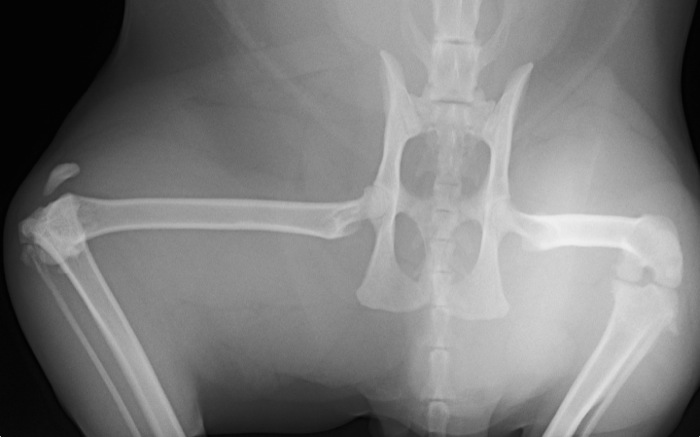

| Pruebas | La radiografía expone una amplia luxación femoro-tibial sin fracturas aunque con una gran inflamación de rodilla. La cápsula parece íntegra. El ligamento cruzado caudal está roto pero el craneal no es valorable. Obviamente en este caso hay grandes limitaciones para la exploración incluso bajo anestesia. |

La radiografía tomada de urgencias con el animal despierto apunta hacia una lesión grave aunque poco clara sobre todo por lo infrecuente de la lesión.